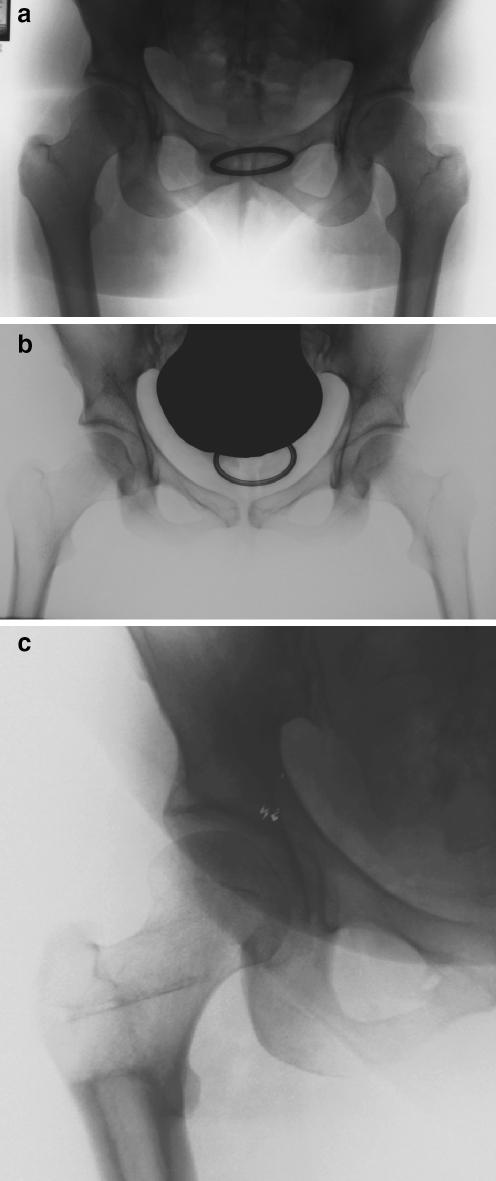

Current literature shows that intertrochanteric osteotomies can produce excellent results in selected hip disorders in specific groups of patients. However, it appears that this surgical option is considered an historical one that has no role to play in modern practice. In order to examine current awareness of and views on intertrochanteric osteotomies among international hip surgeons, an online survey was carried out. The survey consisted of a set of questions regarding current clinical practice and awareness of osteotomies. The second part of the survey consisted of five clinical cases and sought to elicit views on preoperative radiological investigations and preferred (surgical) treatments. The results of our survey showed that most of these experts believe that intertrochanteric osteotomies should still be performed in selected cases. Only 56% perform intertrochanteric osteotomies themselves and of those, only 11% perform more than five per year. The responses to the cases show that about 30-40% recommend intertrochanteric osteotomies in young symptomatic patients. This survey shows that the role of intertrochanteric osteotomies is declining in clinical practice.

https://cdn.ncbi.nlm.nih.gov/pmc/blobs/c5ac/2219926/592e449d6cb3/264_2006_270_Fig1_HTML.jpg